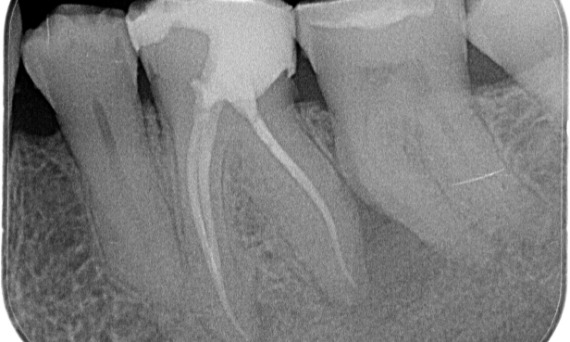

Önce: Öncelikli olarak distal kökle ilişkili periyapikal radyolüsen ve mesiyal kökte lamina dura kaybı.

Sonra: TruNatomy, bu vakada çürüklerden yararlanılan bir yaklaşıma ve özellikle dişin daha minimal bir restorasyona sahip olduğu mesiyal yönde periservikal dentin korumasına odaklanmaya izin vermek için seçilmiştir.